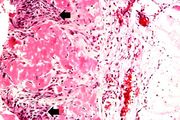

| 04:16, 19 August 2013 | IPLab3ChronicPepticUlcer6.jpg (file) | 92 KB | Seung Park | This high-power photomicrograph of the ulcer base (arrows) demonstrates the lack of epithelium and the exuberant inflammatory response (1) consisting of primarily of fibrin (and adherent gastric secretions) and PMNs. The surface of the ulcer bed is cov... | 1 | |